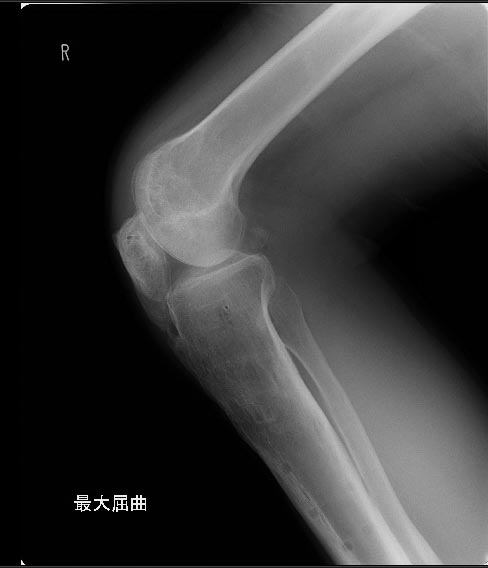

В настоящий момент жалобы на ограничение сгибания в коленных суставах. Снимки прилагаются.

Что можно сделать? У кого есть опыт лечения patella baja?

Чего только на коленках не оперировал,а вот низкое стояние как-то не доводилось. А проблема ведь ни в самом низком стоянии надколенника,а скорее в ригидности собственной связки.(Хочется предложить вентрально-просимальное смещение бугристости с тендораффией сухжилия 4-х главой мышцы и рассечением retinaculum extenzorum и возможно и гемопателляэктомией) Но.. Перед тем как давать советы неплохо бы посмотреть снимки феморопателлярного сустава- по Сеттегасту,Кнудсену итд. Исчерпаны ли все возможности реабилитации?

Высылаю снимки, свидетельствующие, что уровень остеотомий вроде как обычный, повторюсь, подобного осложнения после удлинения я не встречал ни у себя ни

в литературе. Сейчас на первое место встает вопрос как помочь данному пациенту. У кого есть опыт лечения patella baja?

Пациент против оперативного удлинения собственной связки надколенника, и хочет достигнуть цели при помощи аппарата внешней фиксации. Теоретически я представляю как это можно осуществить, но опыта нет. Насколько это эффективно?, Предположительно процесс будет сопровождаться болевым

синдромом... поделитесь мыслями, заранее спасибо.

... загляни в книжки D.Paley: там как раз "про это". Мы используем и методику перемещение при помощи опоры, и используя "спицы-возжи".

Кстати, была оказия обсудить эту тему с Paley и Herzenberg'ом. Если без аппарата, то Herzenberg предпочитает Z-образное удлинение собственной связки. Paley за более сложную реконструктивную операцию - с выкраиванием "бугристностно-надкостничного лоскута" - в деталях, признаюсь, не понял.